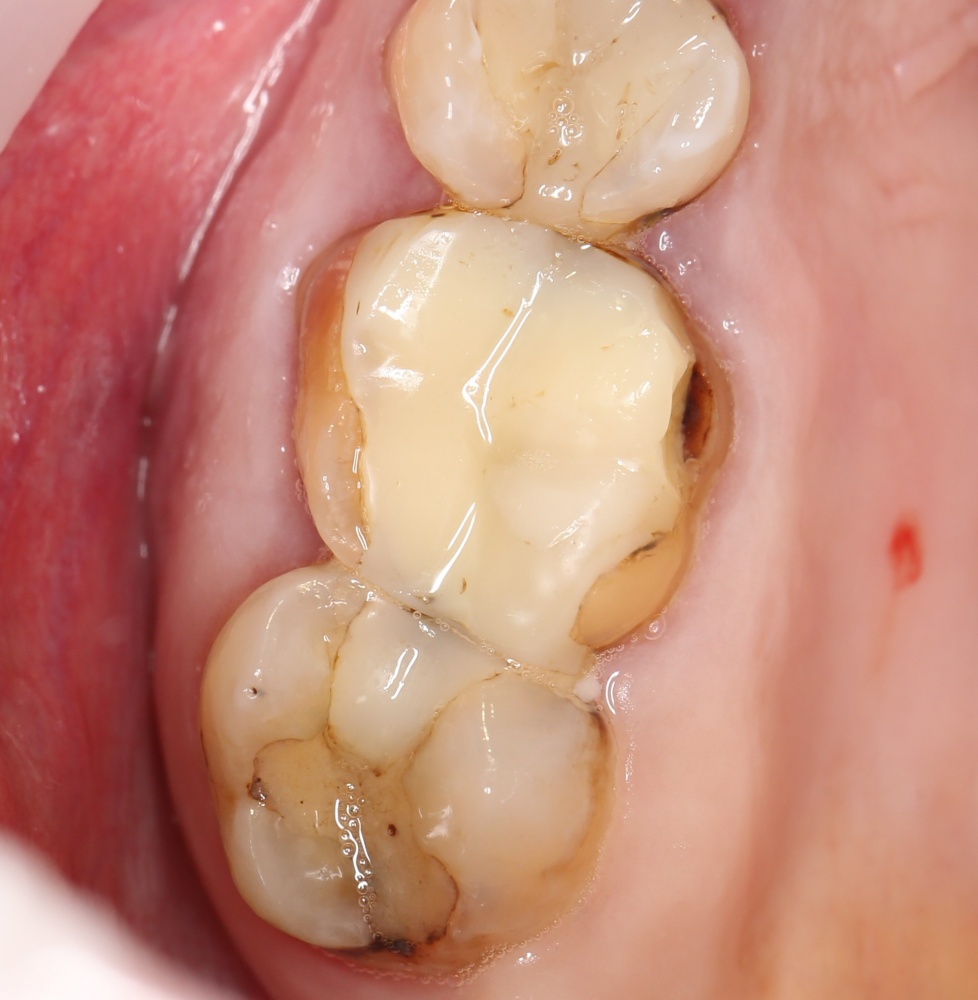

Простой синуслифтинг. Часть I.